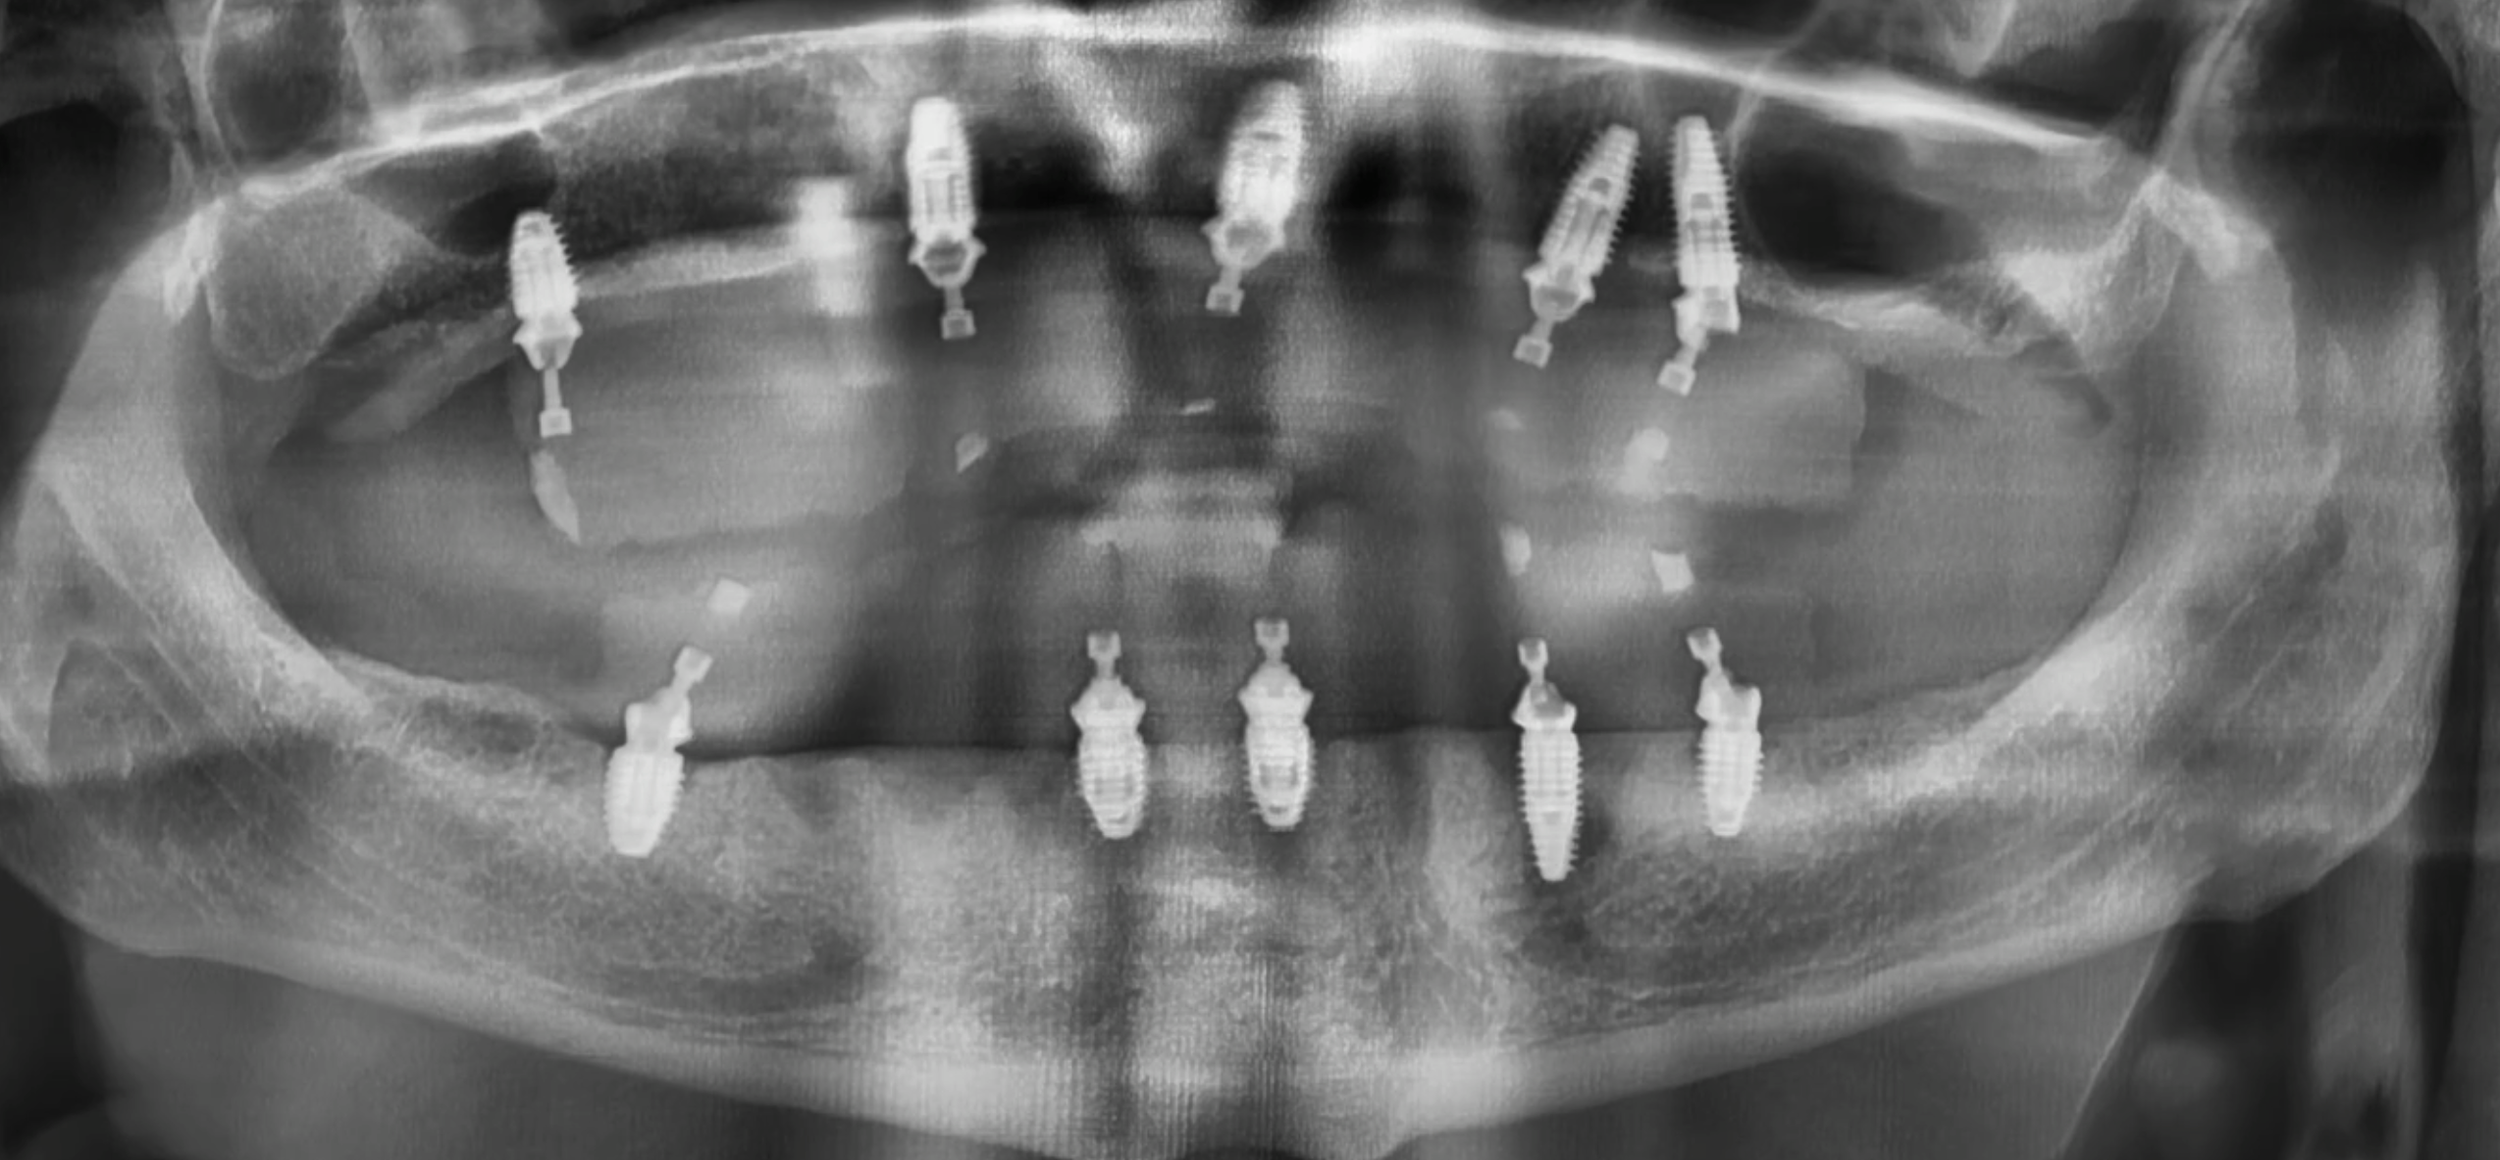

All-on-X uses a small number of strategically placed dental implants to support a full set of fixed teeth. Unlike dentures, these teeth do not come out. They are designed to look, feel, and function like natural teeth. You may be a candidate if you;